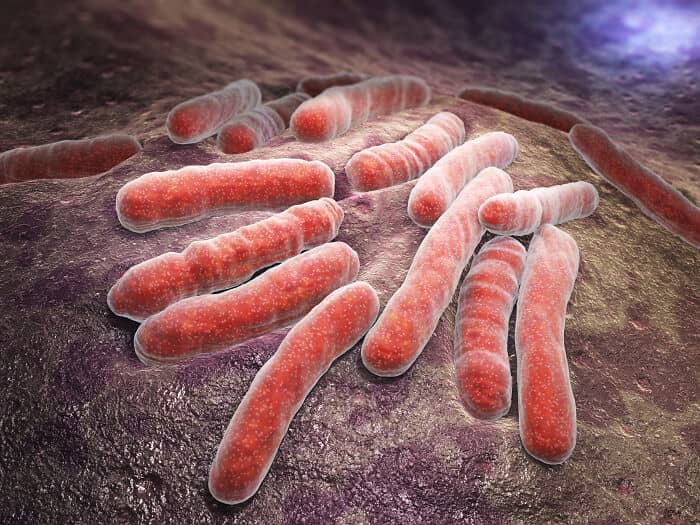

Flesh eating bacteria can quickly lead to amputation and demise. According to the person from whom I learned this terrible ailment from, it’s all but incurable, which reminds me… rabies.

Thinking about how quickly viruses can mutate and spread makes you see everyday germs a bit differently.